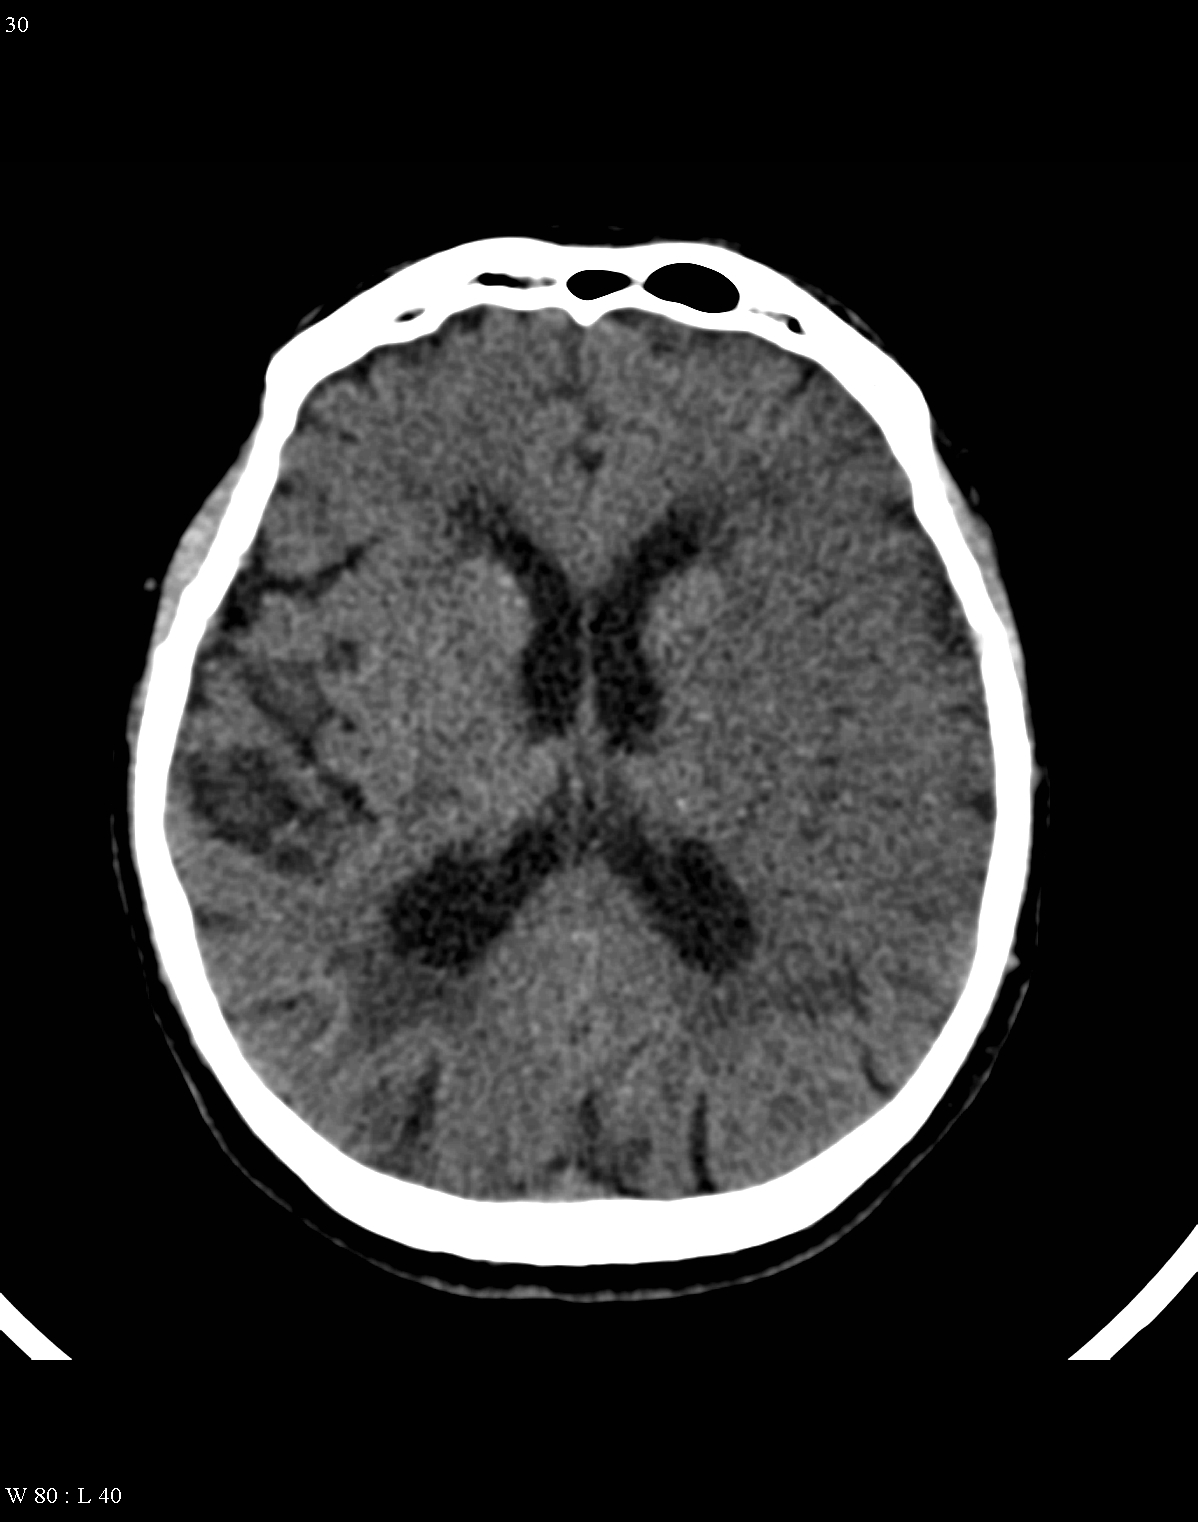

In acute phase (12-24 hours after the occlusion of the middle cerebral artery) on CT hypodense basal ganglia, the loss of cortical white-grey matter differentiation and sulcal effacement are the characteristic imaging findings.

After 1-3 days the “mass-effect” of the infarct increases. It is more apparent in case of large territorial infarcts, the sulcal effacement completes, the loss of cortical white matter and grey matter differentiation is more pronounced (especially in the white matter) due to the increased hypodensity. Hemorrhagic transformation in the grey matter (cortex, basal ganglia) can also occur at this stage. It is worth to note, that for hemorrhagic transformation one should not always blame thrombolytic therapy; it rather occurs spontaneously in a great majority of the cases.

On CT images acute bleeding always presents as hyperdensity. (One has to keep it mind that hyperdensity of the blood is affected by the hematocrit levels, hence making the diagnosis more difficult.) Intraparenchymal blood is dominated by a destructive appearance (mass-effect) and it is surrounded by hypodensity as a sign of perifocal edema. It often breaks into the ventricles. In patients lying in a supine position they collect (sediment) at the occipital horn of the lateral ventricles, creating a hyperdense liquid-to-liquid levels. Later on, the density of blood decreases and shows a peripheral ring or rim-like contrast enhancement without mass-effect.